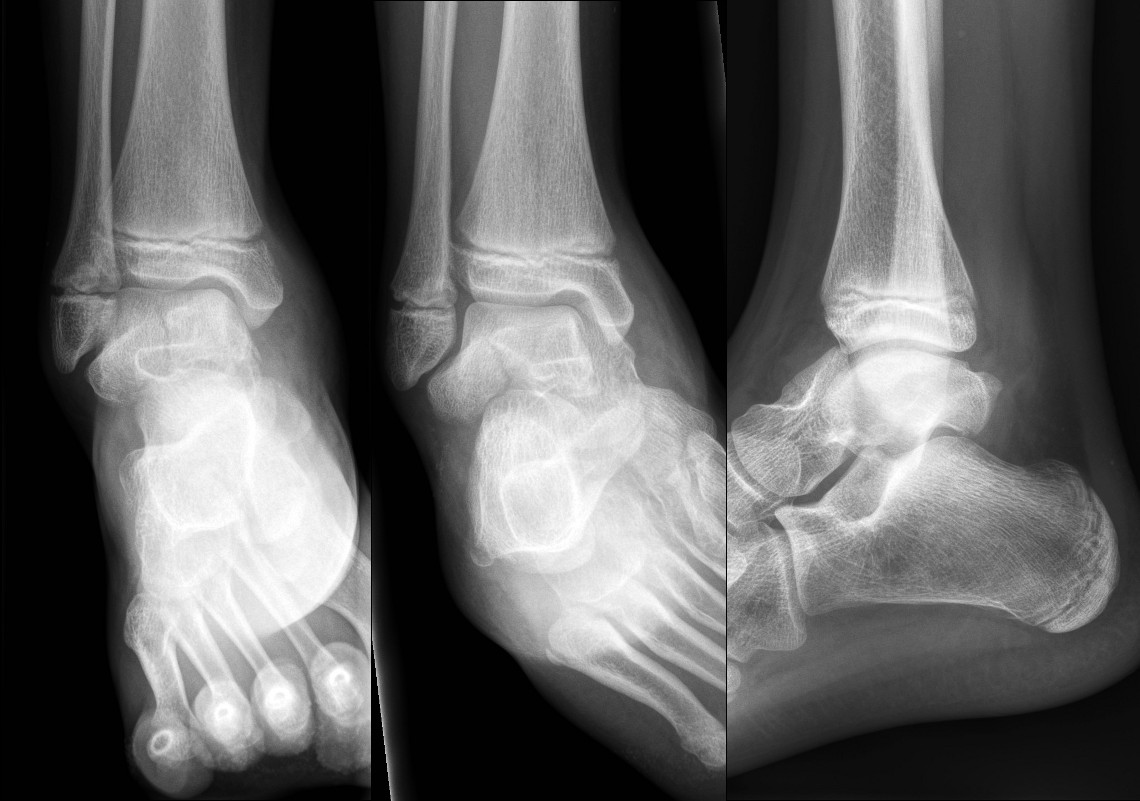

Fracture of neck of talus

Talar dome fracture – looks simple on plain X-ray but CT shows multiple intra-articular bony fragments.